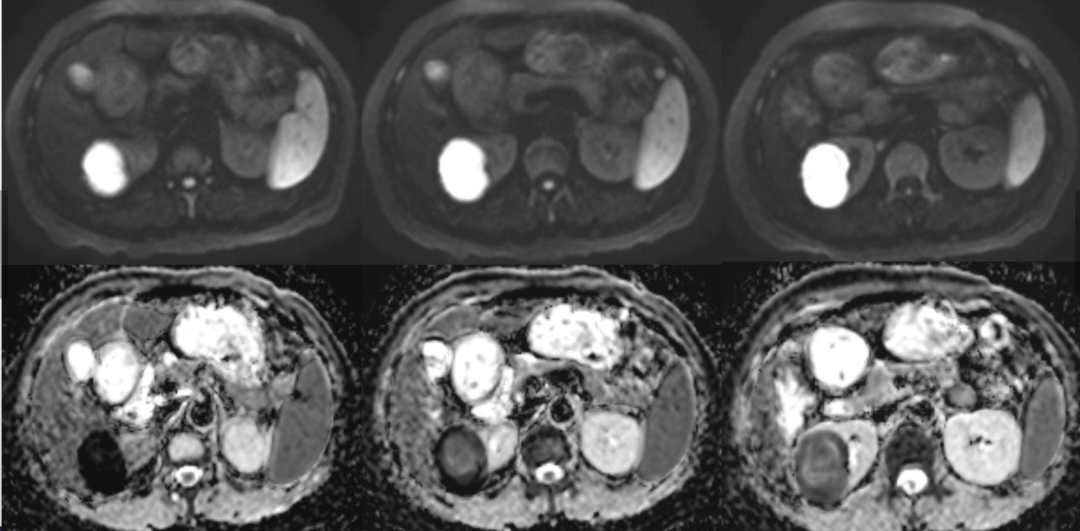

病例1女性,60岁主诉:反复左

病理结果

影像表现为:右肾囊性肿块,肾周无软组织及渗出影,增强囊壁轻度强化,囊内弥散受限明显,不强化,周围有出血